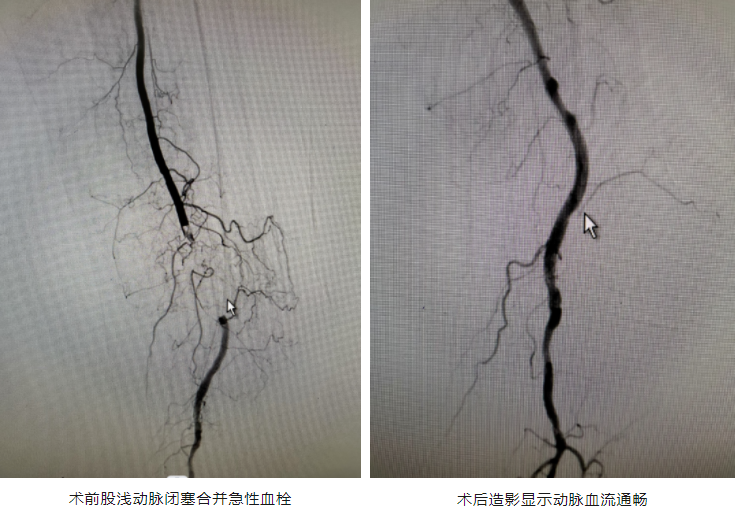

针对患者病情,我院放射科副主任张堃立即组织多学科会诊,制定详细手术方案。6月21日清晨,血管肿瘤介入科谢太喜副主任医师、程瑞文主治医师和曹亚衡主治医师在局麻下为患者先行“下肢动脉造影+溶栓术+血栓抽吸术”,术后疼痛明显减轻,肢体皮温部分恢复。

术后四天,造影复查显示王奶奶下肢血栓消失,但动脉硬化仍导致血管重度狭窄,治疗团队决定二期行“下肢动脉造影术+球囊扩张术+支架植入术“。术后患者血管狭窄消失,并配合中医药活血化瘀、改善微循环等对症支持治疗。术后六天,患者疼痛消失、皮温及颜色恢复正常,康复出院。